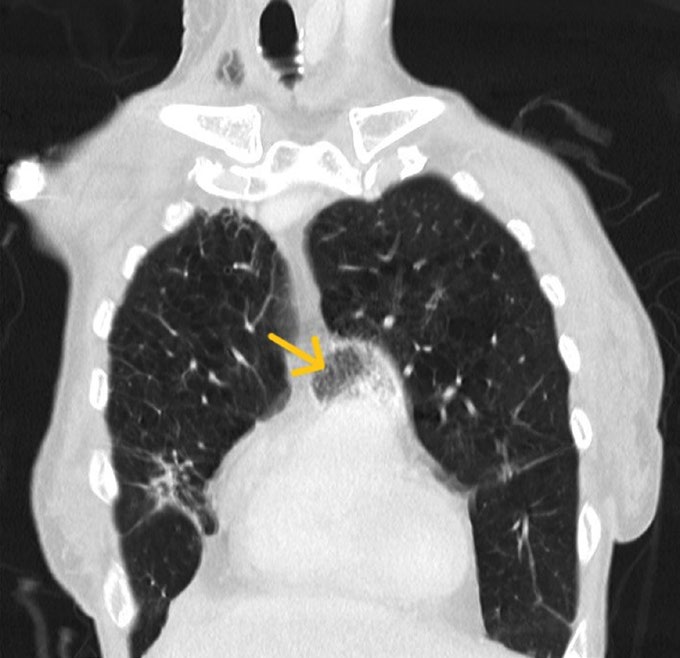

• Pulmonary Arterial Gas Embolism: A Rare Cause of Respiratory Failure

Sérgio Azevedo, Cármen Ferreira, Samba Baldé

107-108

DOI: https://doi.org/10.60591/crspmi.399